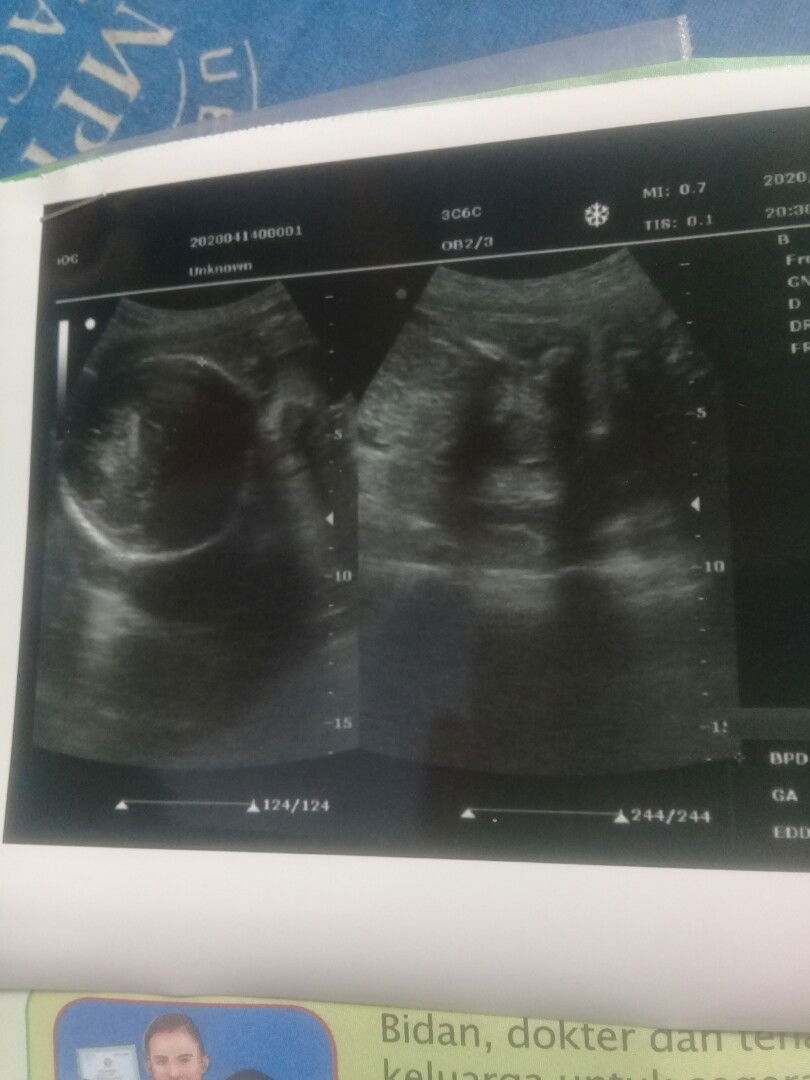

usg 2 dimensi

Hallo buntik, mudah2n kita semua selalu dberi ksehatann amin?? Sharing dong, ada yg pernah berubah ga hsil usg ny, misalny hsil usg laki2 pas lahir perempuan , semlem hsil usg ku laki2 padahal pngen bnget puny anak perempuan, soalny aku sudah puny 2 jagoan hehe Djawab ya bunda2 , terima kasih sebelumny